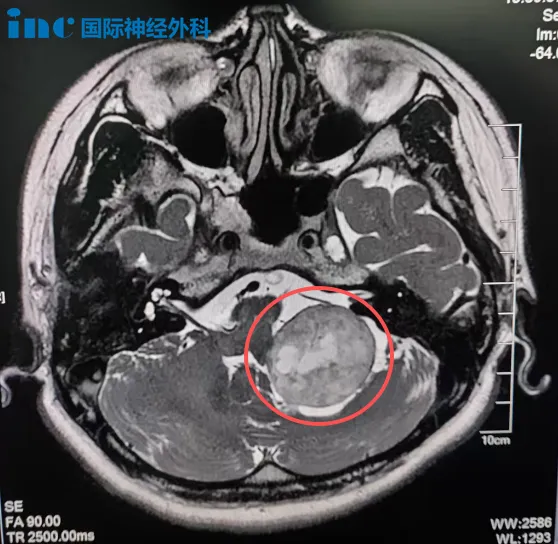

33岁林女士因意外摔倒检查发现左侧桥小脑角区(CPA区)存在36×32mm占位病变。鉴于手术高风险,患者首选射波刀放疗,但治疗后肿瘤未显著缩小,反而出现面部抽搐、眼周跳动伴耳鸣头晕等症状。

巴教授术前评估指出:"尽管既往放疗可能增加神经粘连风险,但我们具备处理此类情况的专业方案。"他形象地比喻手术策略:"肿瘤如同杯体,周围神经好似缠绕的线缆,需要精细分离保护。"最终在苏州大学附属第四医院成功完成肿瘤切除手术。